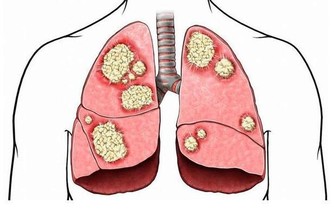

乳癌就是一種壓制不住的糜爛,其末期非常的惡臭,曾有此類病患到我診所,結果此惡臭在室內連續一星期才散去。